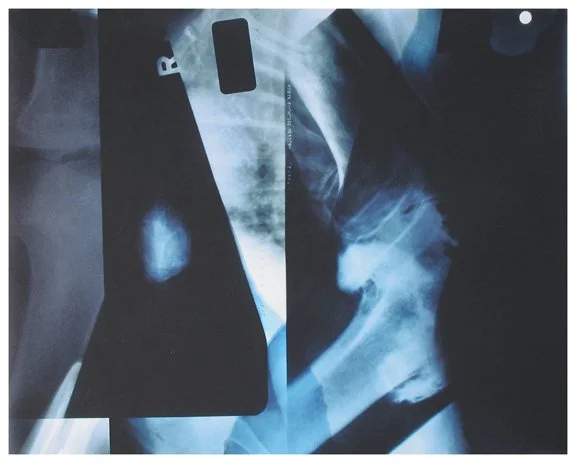

Insight is a series of collaged X-ray fragments, which were digitally composed into giclée prints. They speak not only of the body’s interior, but of the human experience it contains.

Drawn from DNA sequencing gels, mammograms, ultrasound scans, and cell cultures grown in Petri dishes, these compositions reframe diagnostic materials as metaphoric landscapes. What once served to identify illness becomes a language of line, texture, and light. They serve as a quiet meditation on fragility, resilience, and the unseen forces that shape us.

Each image in Insight is both an anatomical artifact and an artistic inquiry. Each one is part of my ongoing exploration of the relationship between Art, Science, and Medicine. Through digital layering and compositional play, I aim to dissolve the boundary between clinical detachment and emotional intimacy by inviting viewers to look inward and find meaning in the microscopic.

Semaphor 9.75" x 9" x 4.75"